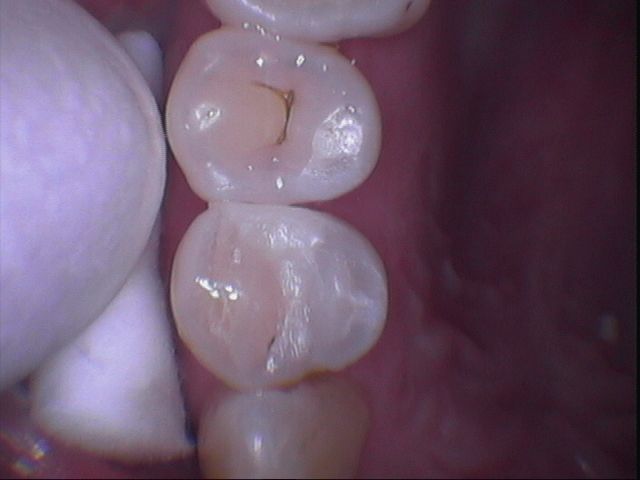

但是樹酯因為強度不足往往一段時間後,產生邊緣龜裂,與二次蛀牙這時候蛀牙範圍往往會比第一次更大,可以使用3D齒雕作修復, 提供牙齒良好的強度與美觀。

圖2較大的蛀洞可使用3D齒雕,保存較多牙齒結構,並提供足夠強度的支撐,恢復牙齒型態與功能。